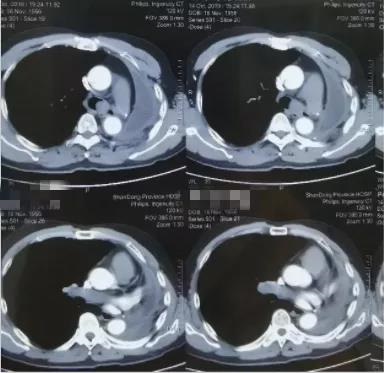

入院时患者胸部CT显示:左肺全切术后残端见新生物生长,且已覆盖隆突,突入气管下段并导致气道中度狭窄。如果不尽快处理,患者呼吸困难会快速进展进而影响生命。

做好充分的术前准备后,在呼吸与危重症医学科主任姜淑娟的指导下,副主任医师龙飞、主治医师王永刚为患者进行手术。气管镜下发现,肿瘤表面血供非常丰富,表面渗血明显,且肿瘤已经越过隆突部分阻塞右主支气管和气管下段。这些表现明确解释了患者术前反复咯血和呼吸困难原因。